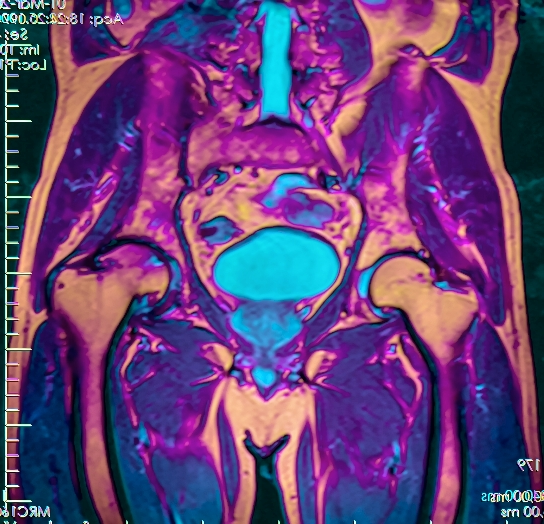

Пациенты часто задаются вопросом, что можно увидеть на МРТ малого таза и какие преимущества у данного метода? Вас могут беспокоить боли в области таза, зачастую это первые признаки серьёзных заболеваний. В этом отделе у человека расположен мочевой пузырь, женские репродуктивные органы и мужские половые органы, лимфатические узлы и кости таза. О причинах и симптомах мы расскажем чуть позже, ну а сейчас остановимся на МРТ исследовании. Что это за процедура и почему она важна для пациента? Магнитно-резонансная томография малого таза это детализированное изображение органов, тканей и крестца на снимке. Процедура необходима для тщательного и качественного обследования внутренних органов малого таза. МРТ позволяет получить информацию о структурных внутренних изменениях в тканях и первичных признаках опасных и серьезных заболеваний. По сравнению с СКТ, на снимках МРТ можно более детально изучить мягкие ткани и всевозможные патологические процессы в них. Вам выписали направление на обследование, но вы не знаете, где делают МРТ органов малого таза? У пациента всегда есть право выбора медучреждения. Сделать правильный выбор клиники и ознакомиться с положительными отзывами, всегда можно при помощи Интернет-ресурсов.

Магнито-резонансная томография (МРТ) — это метод обследования человека, который на сегодняшний день является наиболее точным и безопасным. При взаимодействии электромагнитного поля и разночастотных радиоволн можно послойно рассмотреть положение и состояние внутренних органов и систем, костей, сосудов, структуру тканей, обнаружить возникновение спаек, кист, опухолей и иных патологий. При МРТ органов малого таза исследуются половая и мочевыделительная система, нижние отделы позвоночника, кишечника и расположенные рядом с ними кровеносные сосуды.

Что показывает МРТ малого таза? Исследование позволяет получить снимки последовательных срезов внутренностей с интервалом до 5 миллиметров, создать трехмерное изображение, рассмотреть положение, структуру тканей, выявить патологии на самом раннем этапе их возникновения задолго до появления симптомов.

Поэтому показанием к проведению МРТ малого таза у женщин являются любые патологии, выявленные во время УЗИ-исследования. Магнитно-резонансная томография женского малого таза не только позволяет чётко увидеть все три слоя матки, но и хорошо визуализирует шейку матки, влагалище, придатки, лимфоузлы, прямую кишку и мочевой пузырь.